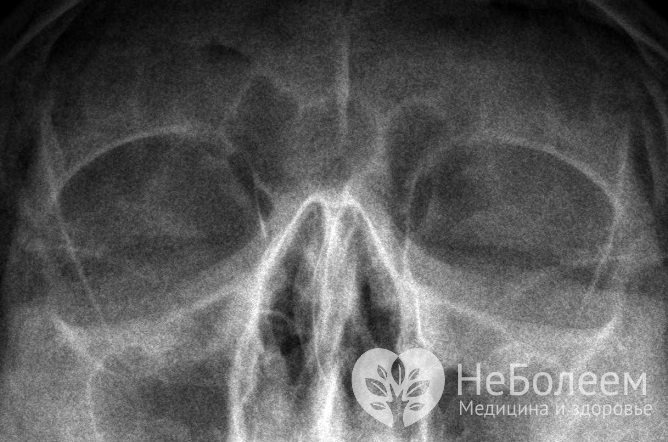

Вазомоторный ринит дифференцируют с аллергическим насморком, синуситом, туберкулезом, склеромой, сифилисом и гранулематозом Вегенера. Для уточнения диагноза обычно назначают рентгенографию придаточных пазух, общий анализ крови и аллергологические пробы. При нейровегетативном рините уровень эозинофилов и иммуноглобулинов класса Е (IgE) остается в пределах формы, кожные пробы дают отрицательный результат. При аллергической форме отмечается эозинофилия и повышенный уровень IgE сыворотки крови, при проведении кожных проб, как правило, удается выявить аллергены. У беременных женщин также определяется исходный вегетативный тонус и гормональный статус организма; особое значение имеют показатели эстрадиола, эстриола и прогестерона – гормонов, оказывающих влияние на нейровегетативные реакции.

Чтобы дифференцировать вазомоторный ринит с другими патологиями ЛОР-органов, проводят рентгенографию придаточных пазух носа Чтобы дифференцировать вазомоторный ринит с другими патологиями ЛОР-органов, проводят рентгенографию придаточных пазух носа